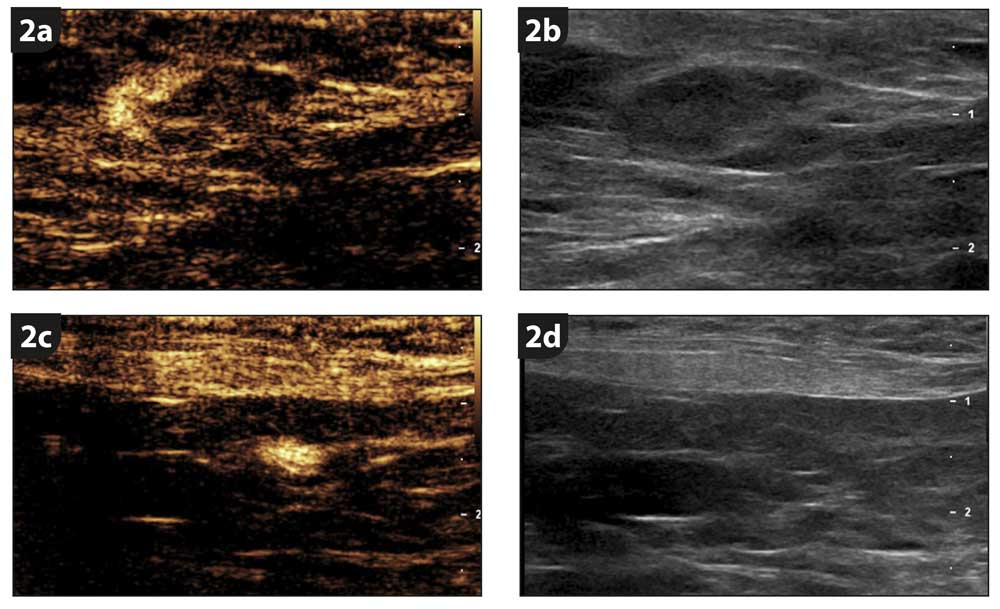

Special advanced ultrasound allowed our radiologist to visualise the contrast real-time, travelling in the lymphatics and first accumulating in the left inguinal LN (in the groin), and after a few minutes also in the left medial iliac LN (inside the abdomen).

The left inguinal LN was moderately enlarged (7mm) with a second, small 2.5mm one, while the left medial iliac LN was within normal limits and too small to be sampled (Figure 2). A fine-needle aspirate of the left inguinal LN unfortunately confirmed it was metastatic, but the liver and spleen were free of mast cells.